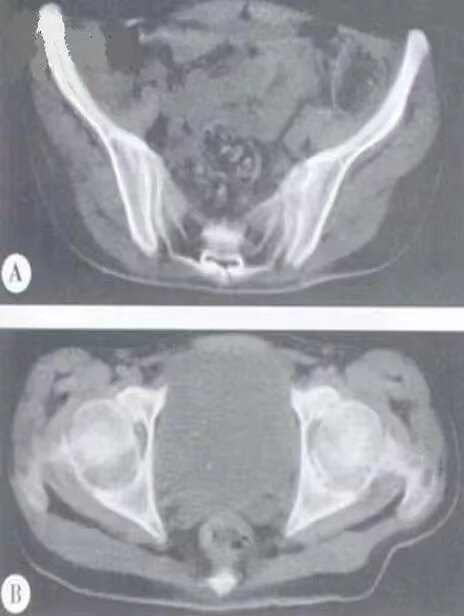

图注:(A)CT示双侧骶髂关节模糊,骨侵蚀破坏,右侧明显,关节间隙无改变;(B) CT示双侧髋关节间隙变窄,关节骨面质破坏呈锯齿状,以髋臼明显。